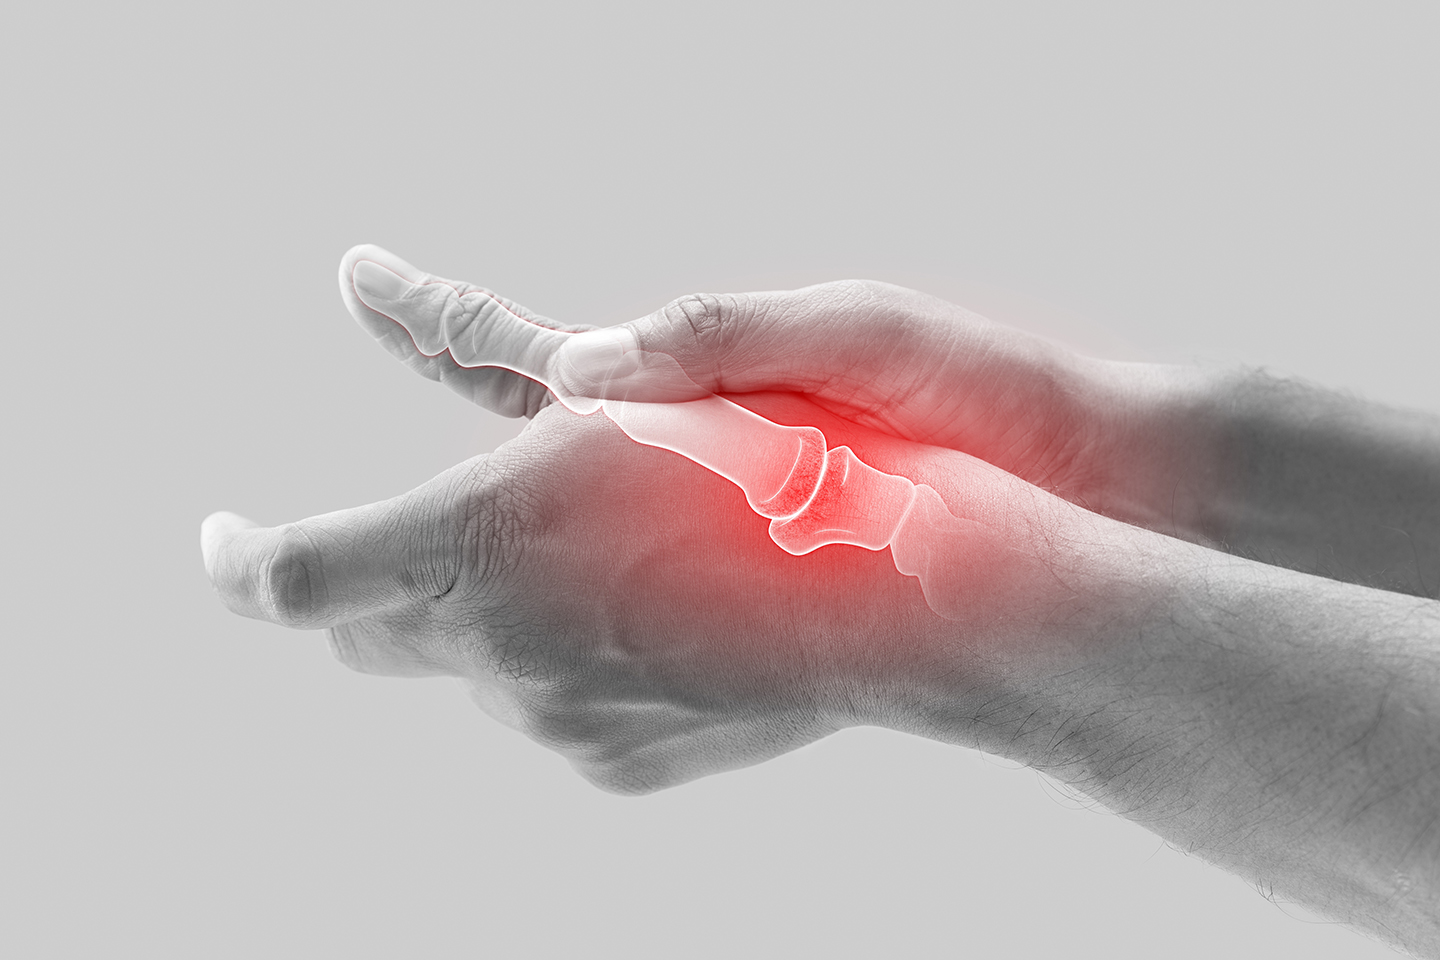

Våra leder utsätts dagligen för både små och stora belastningar. I samverkan med resten av rörelseapparaten – inklusive ben, brosk och liknande – möjliggör våra leder att vi kan kliva upp ur sängen på morgonen, röra oss och utöva sport.

Även om aktiviteter som jogging eller skidåkning utgör en särskild utmaning för knälederna, belastas våra leder intensivt även under vardagliga aktiviteter – till exempel när vi går i trappor. Samtidigt är extra fysisk aktivitet avgörande för att främja våra leders hälsa.

För många som har problem med sina leder kan besvär som daglig obehag, smärta eller till och med något mer allvarligt som artros göra att dessa vardagliga rörelser känns som en ständig kamp.

För att stödja din ledhälsa har en kombination av olika vitaminer, mineraler och växtextrakter visat sig vara effektiv. Den avgörande faktorn: Dessa mikronäringsämnen måste kompletteras specifikt med strukturproteiner som kollagen och sekundära växtämnen.

Den moderna mikronäringsterapin använder kunskapen om de enskilda näringsämnenas effekter för att utveckla kosttillskott baserade på kollagen. Det naturliga strukturproteinet är en huvudkomponent i bindväv, ben, hud och brosk och fungerar som en slags stötdämpare för dina leder.